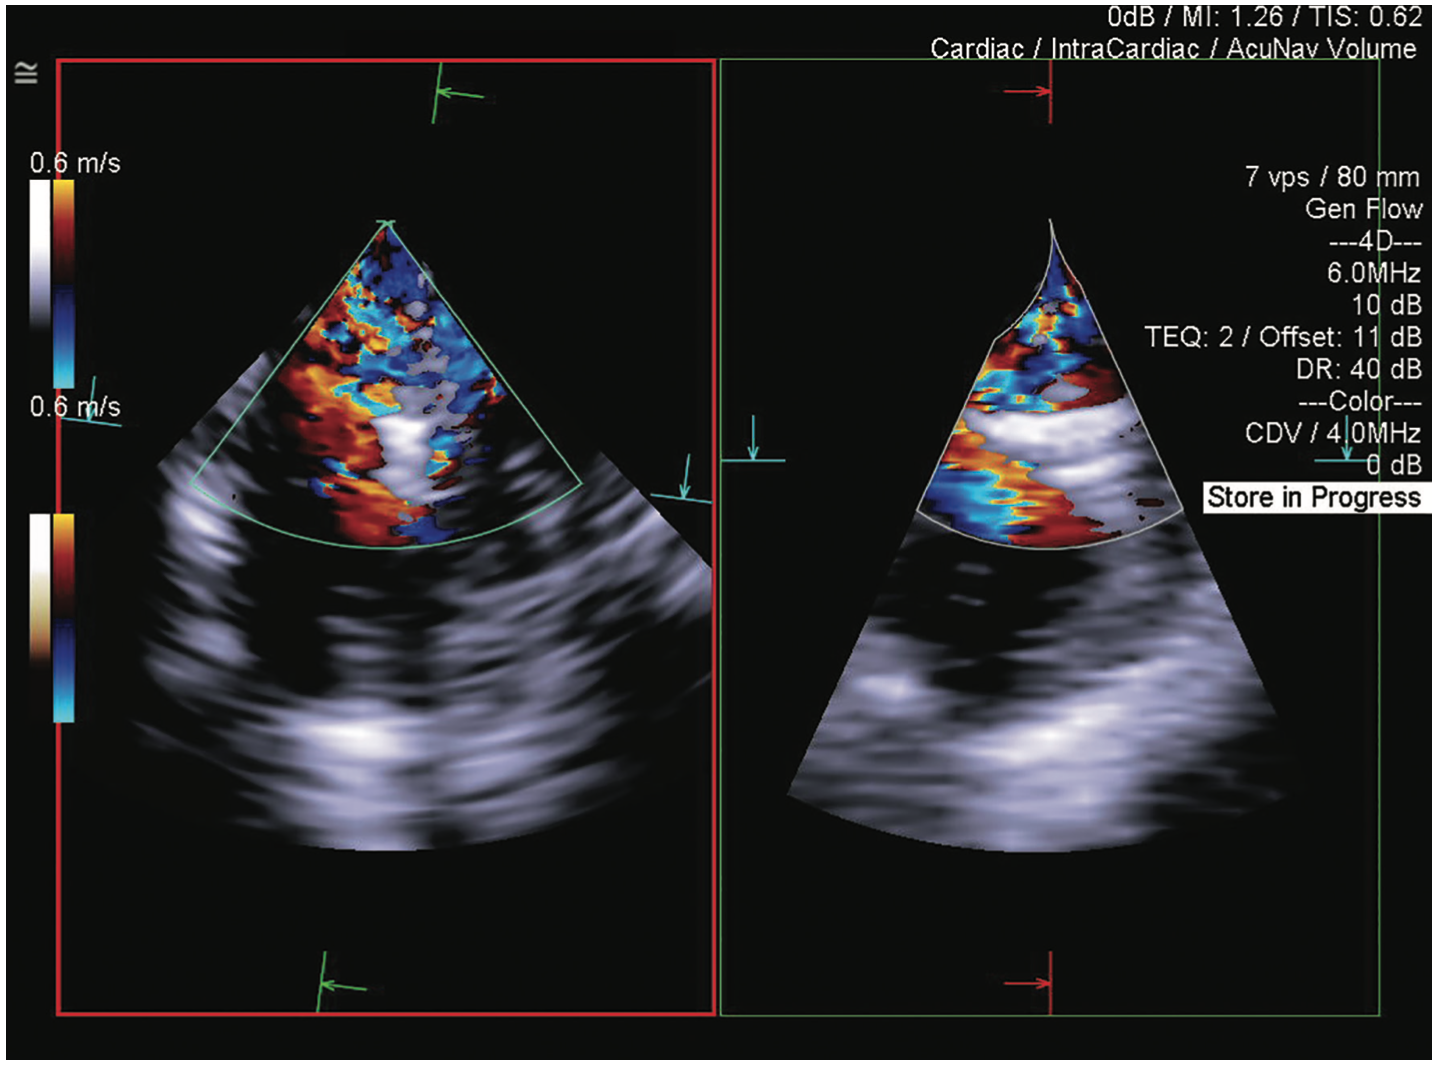

This case of transcatheter edge-to-edge repair (TEER) with a MitraClip device (Abbott) demonstrates how 4D volume intracardiac echocardiography (ICE) catheter imaging (ACUSON AcuNav Volume ICE catheter on the ACUSON SC2000 PRIME ultrasound system, Siemens Healthineers) enables the treatment of patients with severe mitral regurgitation who otherwise would have no options for care.

A 38-year-old female with significant osteogenesis imperfecta, severe scoliosis, and severe myxomatous mitral valve was referred for TEER. An adult transesophageal (TEE) transducer could not be used due to the severe scoliosis, and pediatric TEE imaging was suboptimal for use in the procedure. Preprocedural transthoracic echocardiogram demonstrated severe mitral regurgitation. The 4D ICE catheter assisted with transseptal puncture at the optimal superior and posterior positions, with the circle tool verifying the 4.5 cm distance from the mitral annular plane. Biplane imaging using reference planes with and without color helped guide the device to the optimal position. Physicians were able to treat the patient with relative or absolute contraindication to TEE.